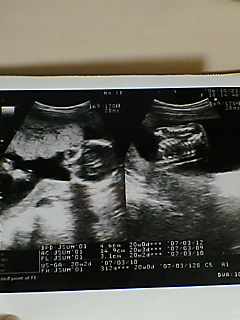

今回は理事長先生担当だったので

赤ちゃんは順調に育っているとの事

貧血気味で尿タンパクが”+”になってしまったので

フェロミアという薬を朝・晩1錠ずつ飲む事になった

(これを飲むとウ○チが黒くなりやすいってお薬です。。。)

今度の妊婦検診は来月(11月)20日で

それ以降は2週間おきに行く事になる